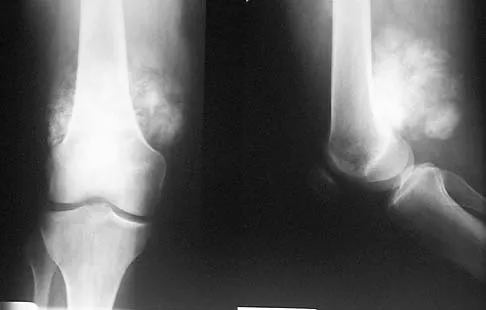

A 58-year-old woman with rheumatoid arthritis and a severe hindfoot valgus deformity now reports recurrent lateral ankle pain. Examination reveals pain over the fibula and sinus tarsi, with a valgus hindfoot that is passively correctable. Despite the use of an ankle-foot orthosis, this is the second time this problem has occurred. Radiographs and a clinical photograph are shown in Figures 28a through 28c. What is the next most appropriate step in treatment?

Excessive hindfoot valgus can lead to abutment between the calcaneus and fibula. This valgus force can lead to a stress fracture of the distal fibula. Surgery may be required if an insufficiency fracture recurs despite orthotic management. Of the choices listed, a subtalar arthrodesis is most likely to achieve rebalancing of the foot at the level of the deformity. Stephens HM, Walling AK, Solmen JD, Tankson CJ: Subtalar repositional arthrodesis for adult acquired flatfoot. Clin Orthop 1999;365:69-73